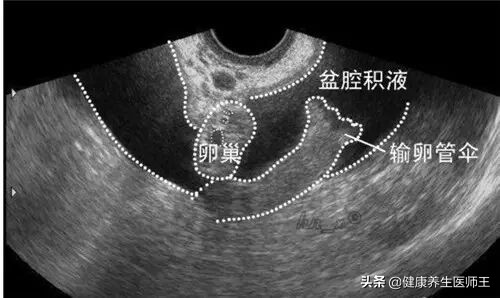

阴道超声或磁共振检查量示输卵管增粗输卵管积液,

伴或不伴有盆腔积液输卵管卵巢肿块,